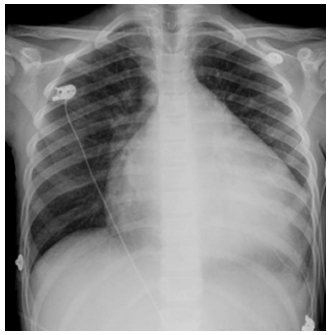

No raciocínio clínico, é importante o conjunto da anamnese, exame físico e exames complementares, eventualmente solicitados. Considere uma pessoa assintomática, em avaliação de rotina, para a qual foram solicitados exames gerais. A radiografia de tórax trazida é a disposta abaixo. Analise-a.

Com base, unicamente, na radiografia acima, podemos inferir que: